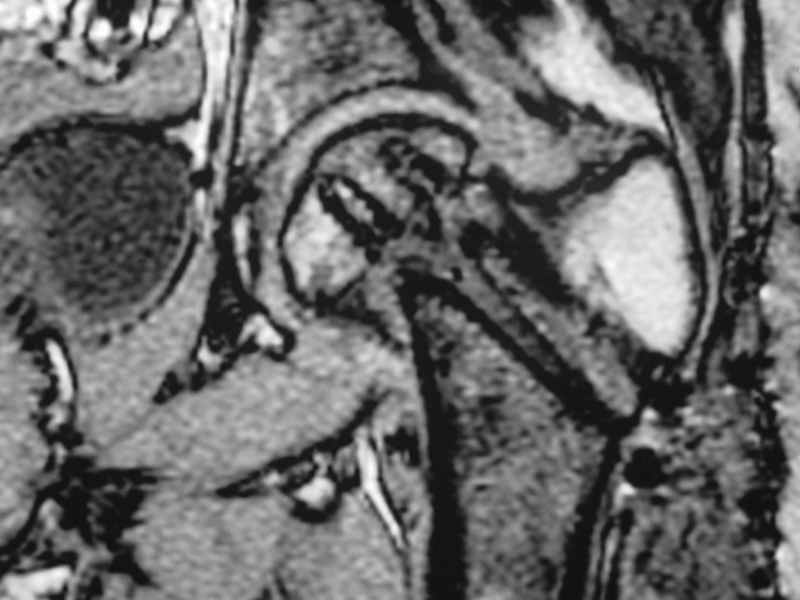

Erden K?l?c 16 Октябрь 2005, 00:03

I would leave it as it is. Because surgical intervention will not be able to prevent osteonecrosis if it is going to be. MRI may be helpful to determine union if there is any and also gives an idea about the viability of the head.

Stephen Kottmeier 17 Октябрь 2005, 21:05

integrity consider establish vascular status via mri

Отправитель: Peter Trafton 17 Октябрь 2005, 21:21

I think that this 31 yo deserves a try with valgus osteotomy, as so nicely illustrated by stephen kottmeier. However, I'd do it no matter what an MRI shows - thus why bother with the MRI? (What sort of data support MRI's ability to predict segmental collapse?)